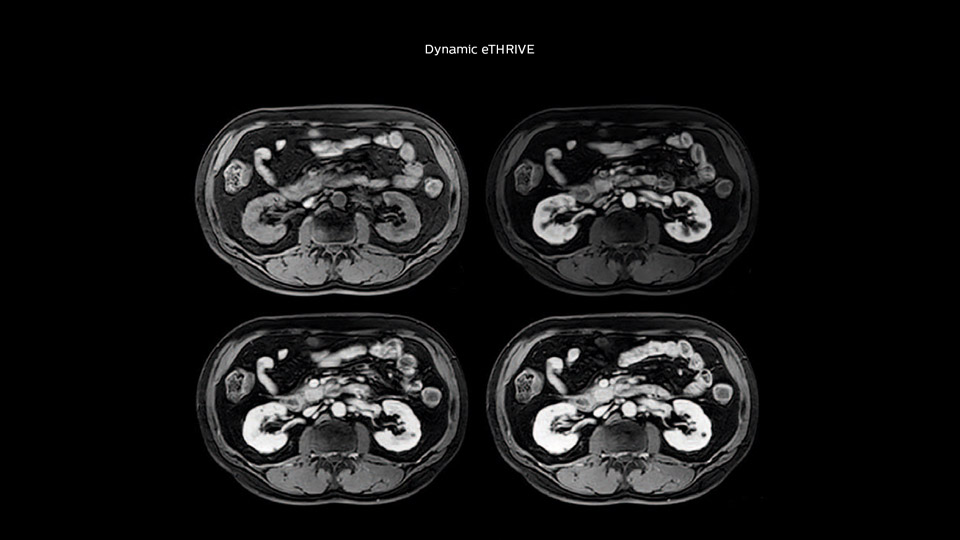

“We include mDIXON for the dynamic sequences because of the robust and homogeneous fat suppression we get with that. We had been using eTHRIVE, but we are now quite happy with mDIXON. Sometimes we use a medication to calm the bowels, to further improve the image quality.”